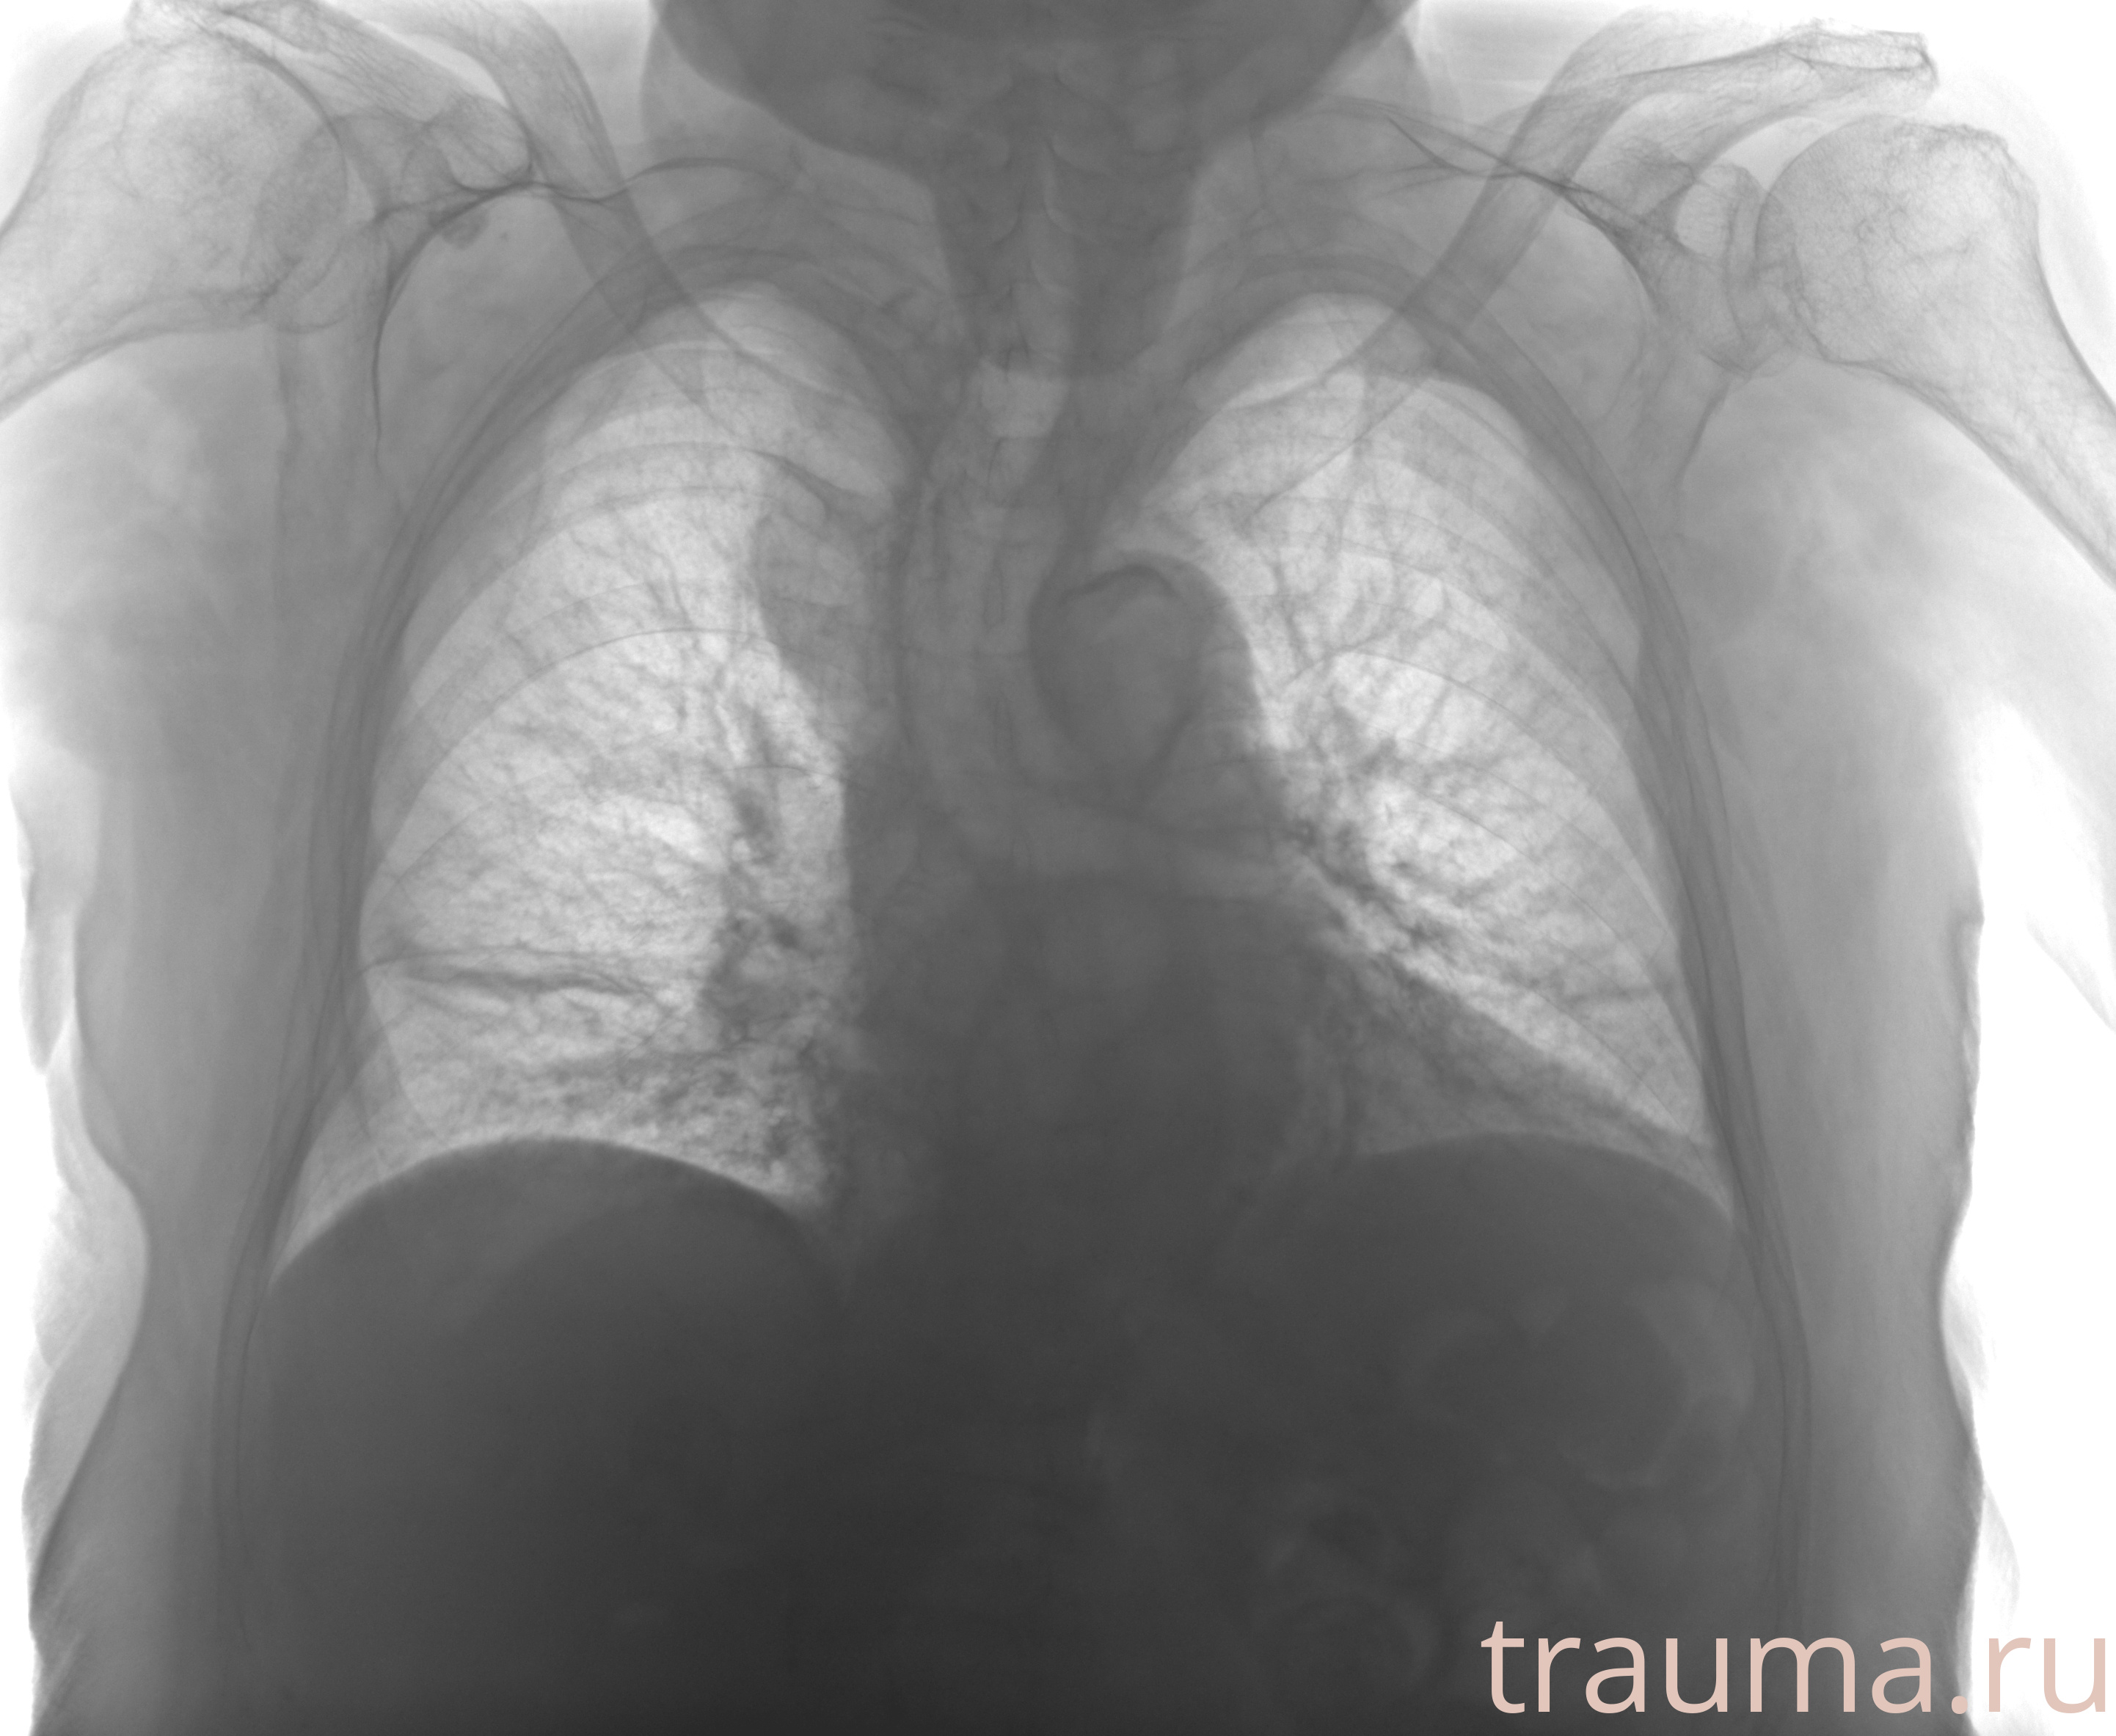

Перелом 3-5 ребер слева